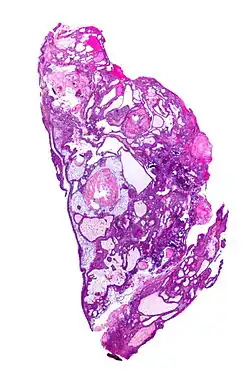

On macroscopic examination, craniopharyngiomas are cystic or partially cystic with solid areas. On light microscopy, the cysts are seen to be lined by stratified squamous epithelium. Keratin pearls may also be seen. The cysts are usually filled with a yellow, viscous fluid rich in cholesterol crystals. Of a long list of possible symptoms, the most common presentations include headaches, growth failure, and bitemporal hemianopsia.

-

Micrograph showing the characteristic features of an adamantinomatous craniopharyngioma - cystic spaces, calcifications, and "wet" keratin, HPS stain -